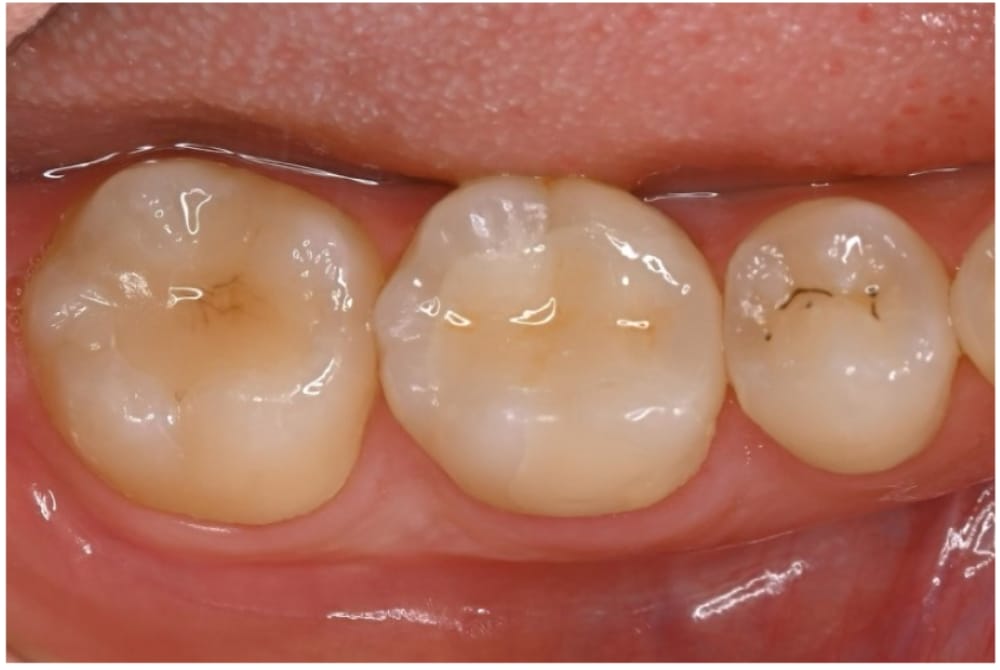

治療後12ヶ月

セラミックインレー装着後の状態です。歯髄保存療法から12ヶ月が経過しており、日常生活でも支障はなく、健康な状態を維持できています。